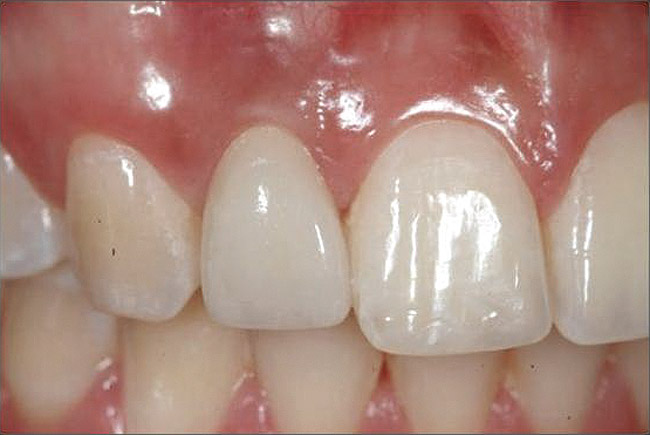

Figure 1  Critical bone and soft tissue relationships: The position of the buccal bone crest is approximately 3 mm from the gingival zenith of the natural tooth. Recapitulation of this architecture for ideal single-tooth implant esthetics requires that the adjacent bone crest approximate this level in three dimensions. Implant placement at the crest will support the formation of 3 mm of supracrestal buccal soft tissue, which embodies the suclus and the junctional epithelium/connective tissue contact along a titanium or zirconia abutment.

Figure 1

Esthetics is a crucial concern for anterior dental restorations. In addition to the aforementioned volumetric osseous support of osseointegration, the location of the implant in the alveolus must be further considered in terms of esthetics. The relationship of the implant, the implant/abutment interface, and the enveloping bone are considered to be critical determinants of the soft-tissue form surrounding the dental implant crown. One approach to assuring the esthetic integration of the implant with existing teeth is to attempt to recapitulate the peri-coronal tissue architecture by the peri-implant mucosa that is formed at the implant (Figure 1). This approach demands that bone is present in the crestal region of the alveolus to support the soft-tissue form at the buccal aspect of the implant. Achieving reproducibly esthetic implant crowns requires management of these important relationships.